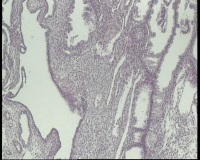

| 图片: | |

- 急!请老师看看34岁子宫内膜

| 性别 | 女 | 年龄 | 34岁 | 临床诊断 | 子宫内膜息肉? |

| 一般病史 | 末次月经:11月20日,近两个月无诱因性生活有阴道少许血性分泌物 | ||||

| 标本名称 | 宫内容物 | ||||

| 大体所见 | 膜样碎组织3.0厘米 | ||||